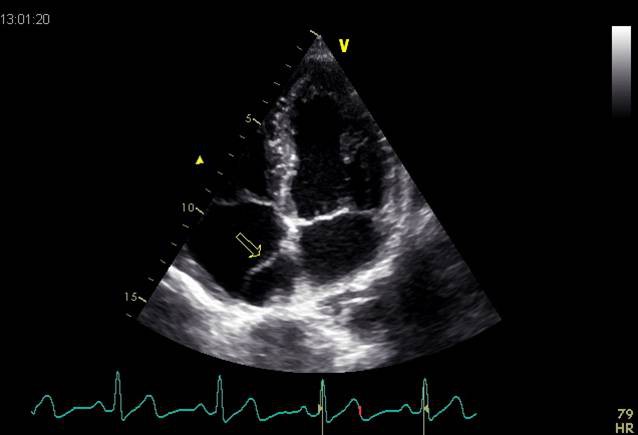

Vorhofthrombus: Thrombus an der Lateralwand des linken Vorhofs (Typ-B-Thrombus; Pfeil Schrittmacherelektrode; Doppelpfeil Thrombus; apicaler Vierkammerblick) |